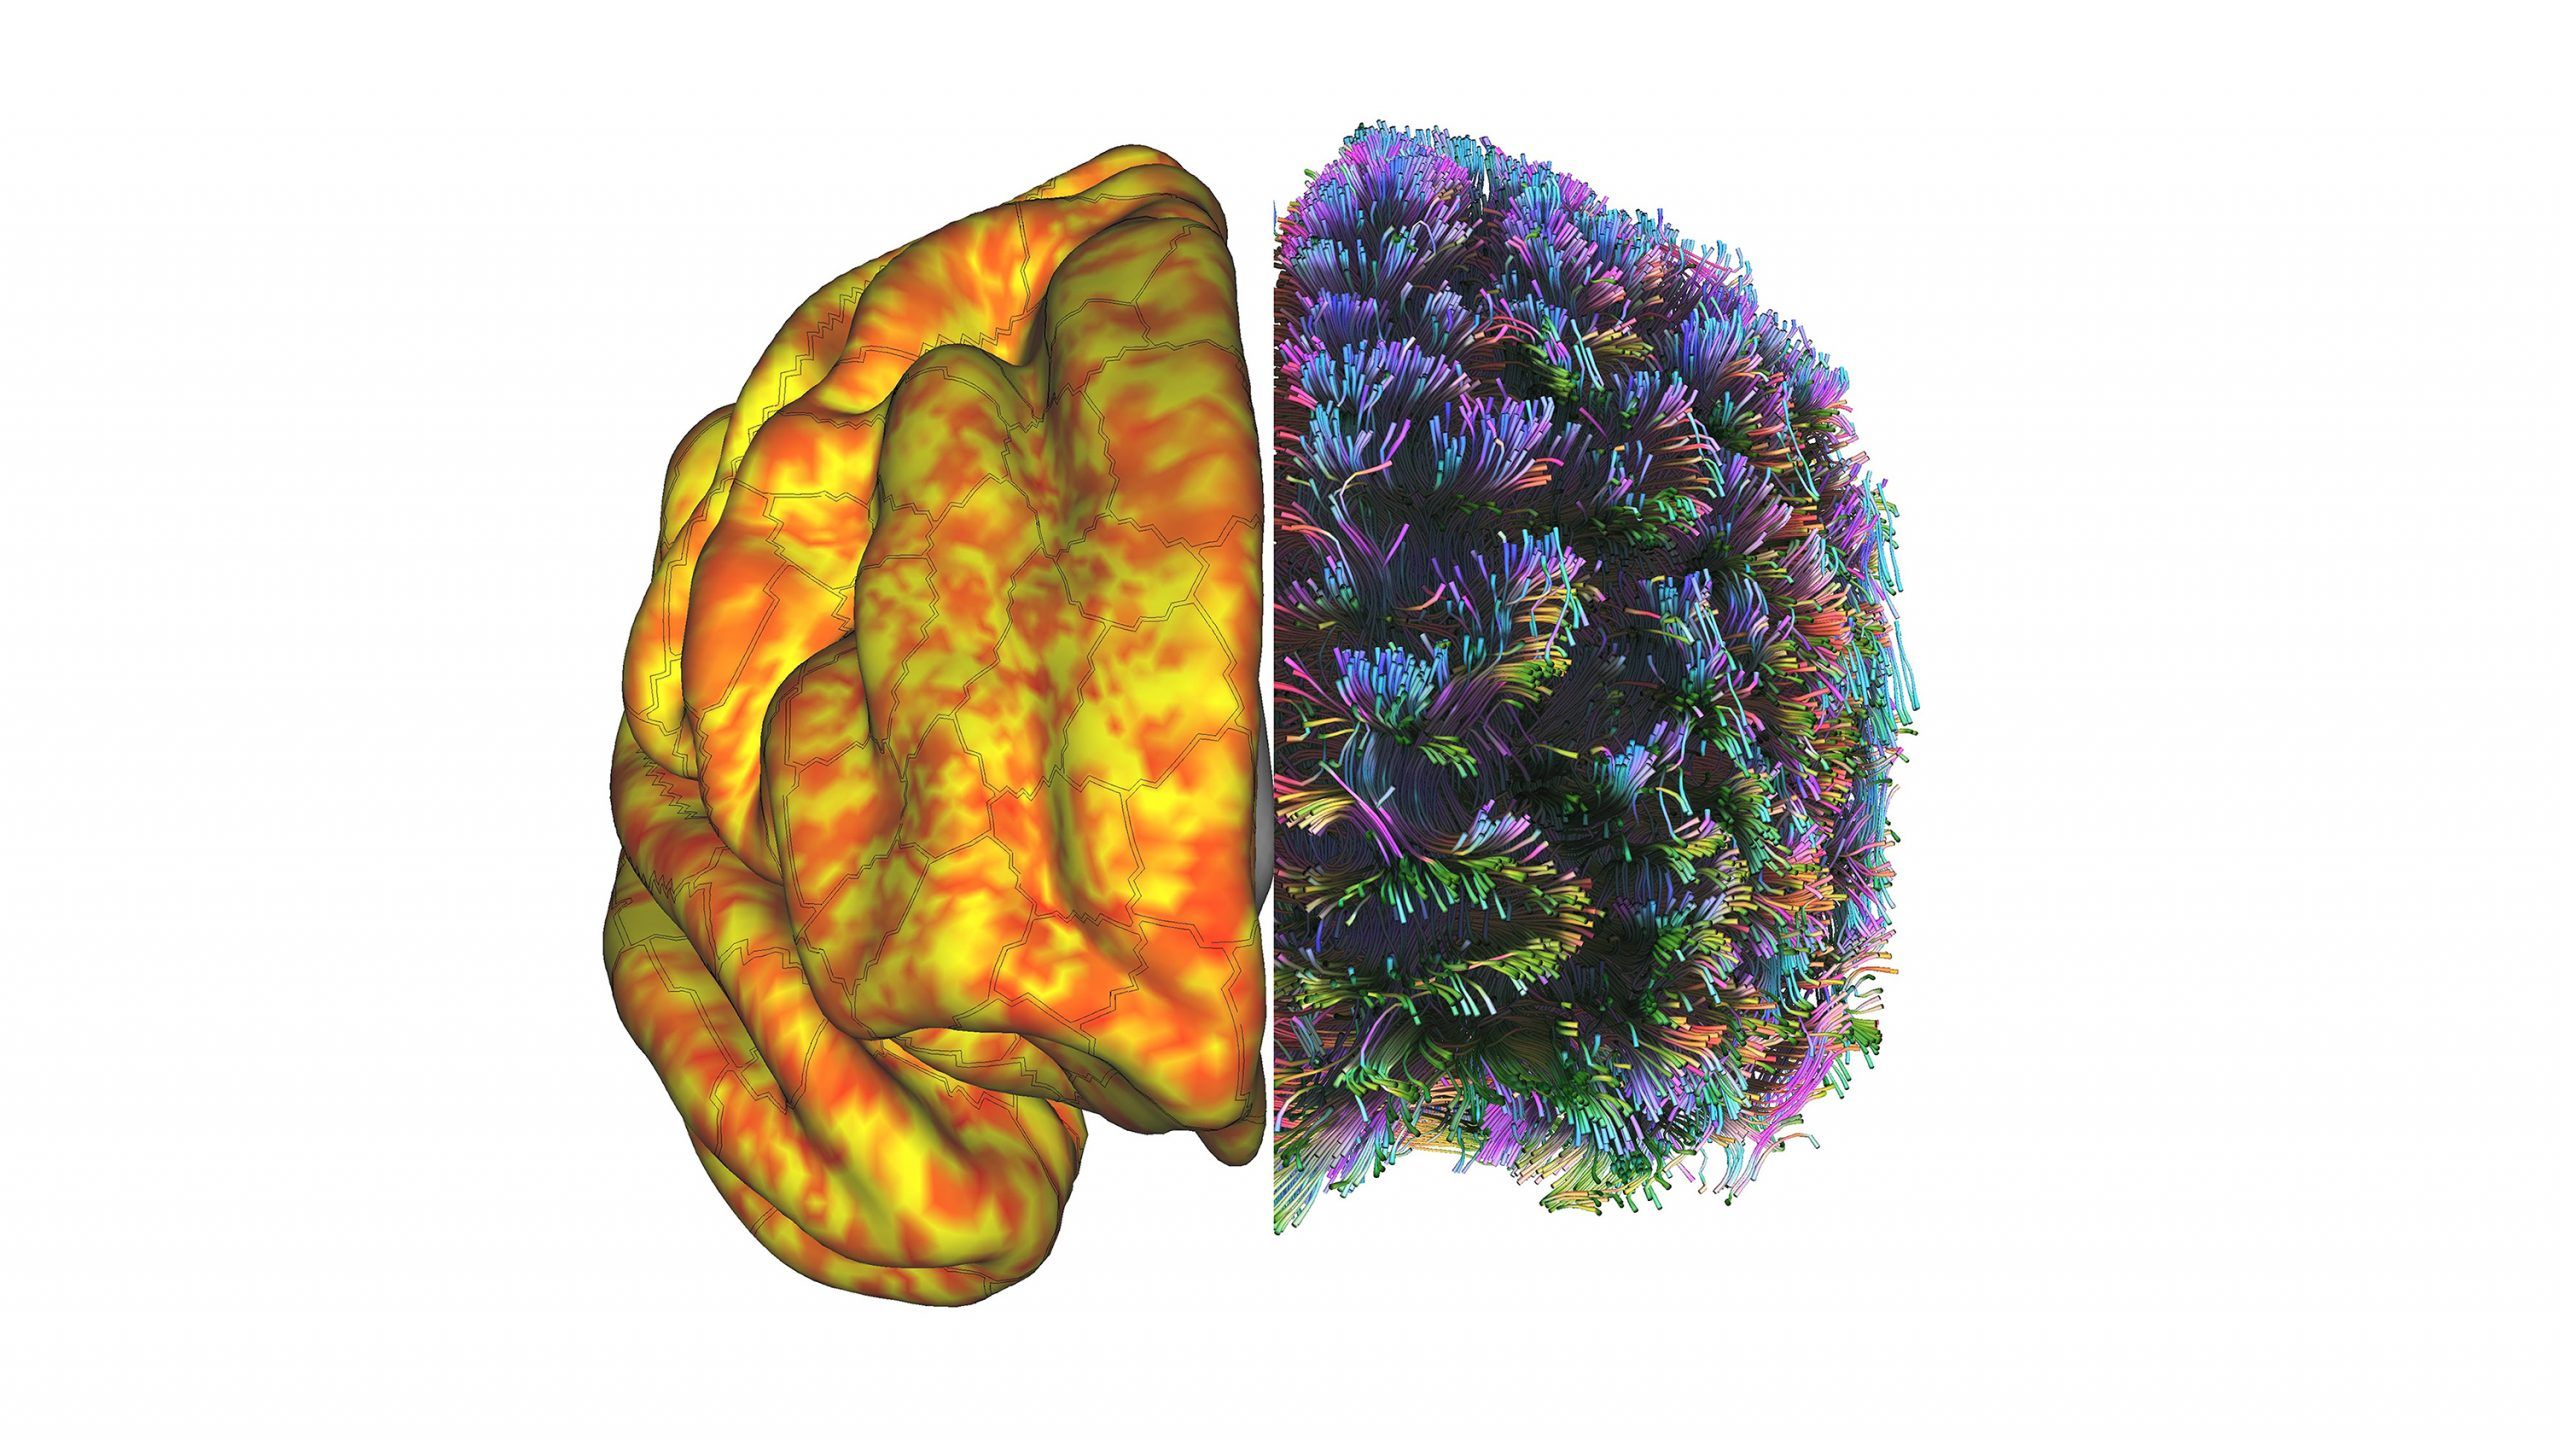

UNCG researchers are using a magnetic resonance imaging machine, or MRI, to peer inside joints and take pictures of study volunteers’ brains. Their goal is to better understand how our bodies and brains function – and why things go wrong – to find ways to prevent common problems.

MRIs create high-resolution images of tissues that have water in them – virtually all tissues in the human body.

Powerful magnets in the machine cause protons in water molecules to align, and then the machine emits radio waves that tickle those water molecules. The water molecules give off energy the machine detects to create pictures of tissues. It can even measure blood flow in the brain.